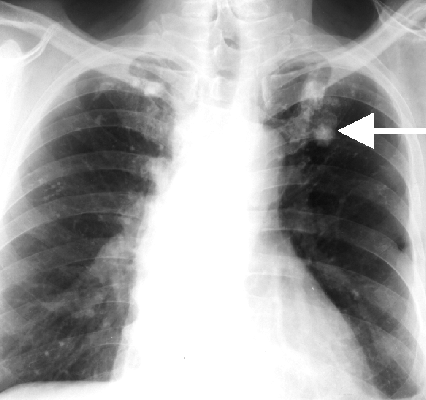

Симптомы туберкулеза: Как распознать и что делать